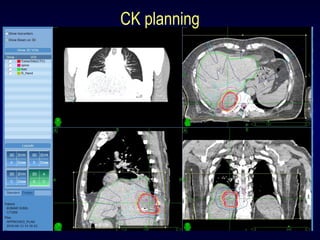

Planning & treatment execution

Contouring:

CT scan & MRI scan fusion

Occasionally PET scan fusion

Target (GTV) & critical structures contoured

(liver, duodenum, small intestine, kidney)

PTV margin ≅ 2 mm

Planning done: on Multiplan

Plan approved as per:

1.Target coverage

2.Critical structure dose

3.Nodes / beamlets / MU / time

Critical structure constraints as per protocol

copyright@www.radiosurgery-india.com

CK planning